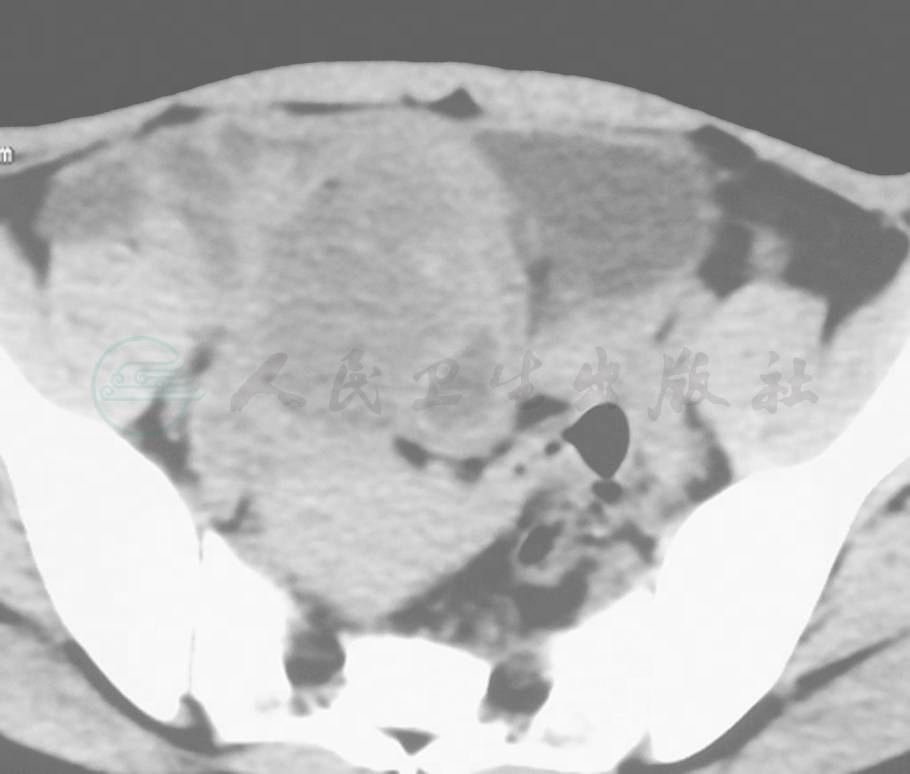

右侧附件区占位性病变,(图1,2)

图1 右侧附件区可见囊实性病灶

图2 右侧附件囊实性病灶